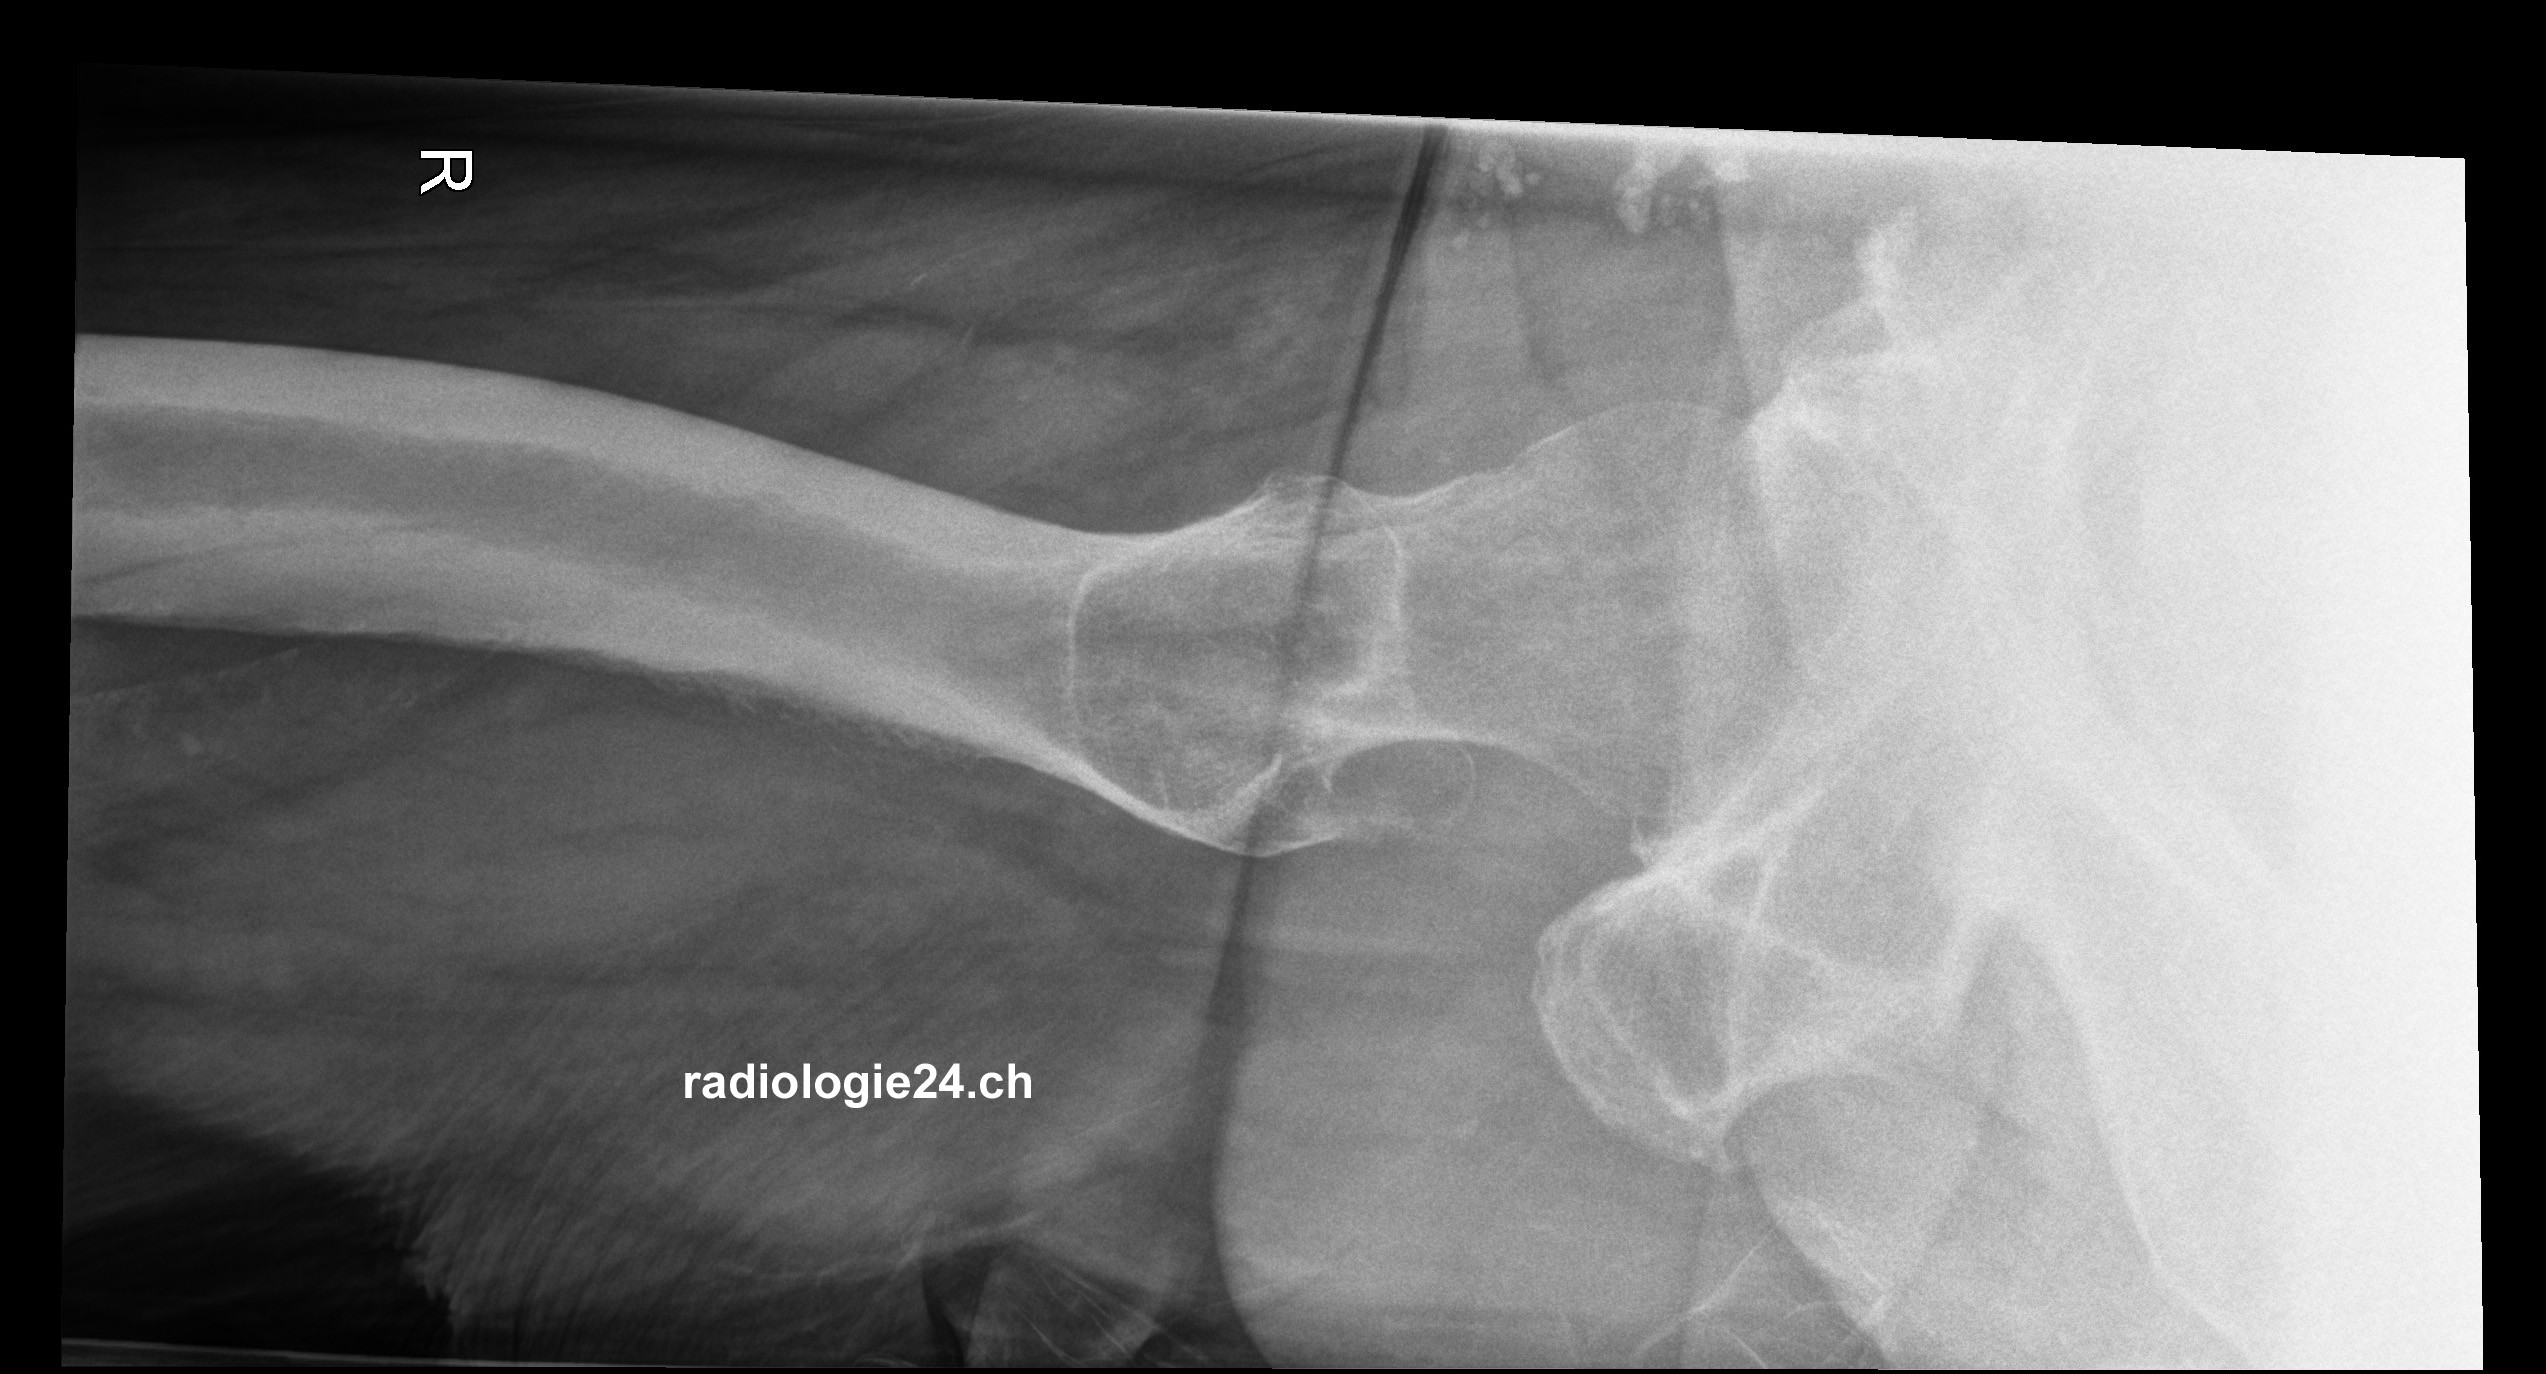

Röntgenfall des Monats August 2017 mit Auflösung

75 jähriger Patient therapierefraktäre Becken-/Hüftschmerzen rechts Diagnose/weitere radiologische Diagnostik?

Bild vergrössern